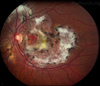

What are the findings in this patient?

1. Diffuse retinal whitening 2. Cherry red spot 3. Macula relatively preserved (supplied by cilioretinal artery) 4. Retinal attenuation 5. Ghost vessel inferotemporally

What are the investigations for a patient with CRAO?

1. OCT - inner retinal hyper-reflectivity 2. FFA - delayed arterial filling 3. Check for NEOVASCULARISATION Ocular massage, breathe in bag (for CO2, vasodilator) Bloods 1. ESR/CRP - rule out GCA Systemic investigations 1. Carotid Doppler 2. ECG/Echocardiogram **Urgent stroke referral for embolic cause**